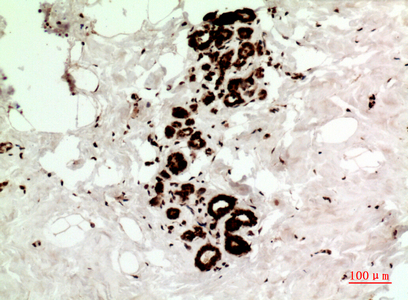

IHC (Immunohiostchemistry)

(Immunohistochemical analysis of paraffin-embedded human-Breast-cancer, antibody was diluted at 1:100)

IHC (Immunohistochemistry)